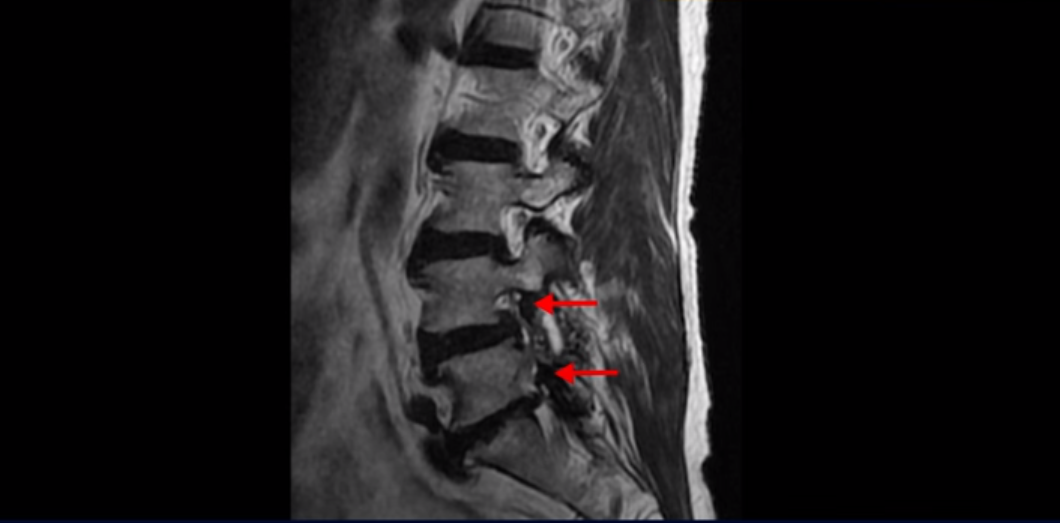

이분 MRI 보면서 설명드린 후 왜 이분처럼 발병한지 얼마 안된 협착증이 치료가 정말 빠르고 쉬운 건지 또 치료는 어떻게 하는 건지 자세히 설명 드리도록 하겠습니다.

MRI를 보면 척추 여러 마디가 퇴행되어 있고

척추관도 좁아져 있고

특히 왼쪽 신경가지가 빠져나가는 4번 5번, 5번 1번 추간공들이 많이 좁아져 있습니다.

이분이 처음 아프게 된 건 작년 말입니다. 그런데 만일 이분이 아프기 전인 작년 초에 MRI를 찍었다면 지금 보시는 MRI와 많이 다를까요? 정답은 거의 차이가 없다입니다. 노화로 인해 신경 구멍이 좁아진 건 이미 오래 전에 벌어진 일입니다. 이렇게 신경 구멍이 좁아져 있는 채로 아무런 증상을 느끼지 않고 최소 5년에서 10년 이상 잘 산 것입니다. 이런 걸 잠복 협착이라고 합니다. MRI로 협착이 보이지만 아무런 증상이 없다는 뜻입니다.

그럼 왜 작년 말에 갑자기 아프게 된 걸까요? 바로 근육에 문제가 생겼기 때문입니다. 60세 넘어서 근육이 줄어들고 약해진 상태에서 무리한 일이나 운동 등으로 근육에 문제가 생기면 허리를 잘 지지하지 못하니까 신경이 자극되고 눌리는 증상이 생기는 겁니다. 신경 구멍이 좁아져 있으니까 근육에 문제가 생기면 신경 자극 증상이 더 쉽게 나타나는 겁니다. 이분은 영상에는 없지만 작년 겨울 스키를 타다 넘어졌다고 했습니다. 아마 그게 근육문제를 일으켰고 발병에 영향을 주었을 가능성이 높습니다.